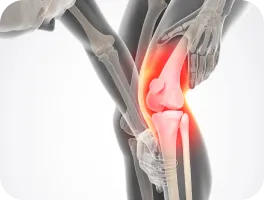

안짱다리인 상태에서 억지로 발레동작으로 발끝을 바깥쪽으로 돌려 걷게 하면 고관절이나 무릎 관절 주위 근육, 인대에 무리한 부담을 주고 관절의 손상을 초래할 수도 있습니다.

무릎과 대퇴골이 내회전 된 경우에는 발레로 좋은 결과를 얻기도 하지만,

무릎 통증

관절염 유발

• 무릎 통증이 있다.